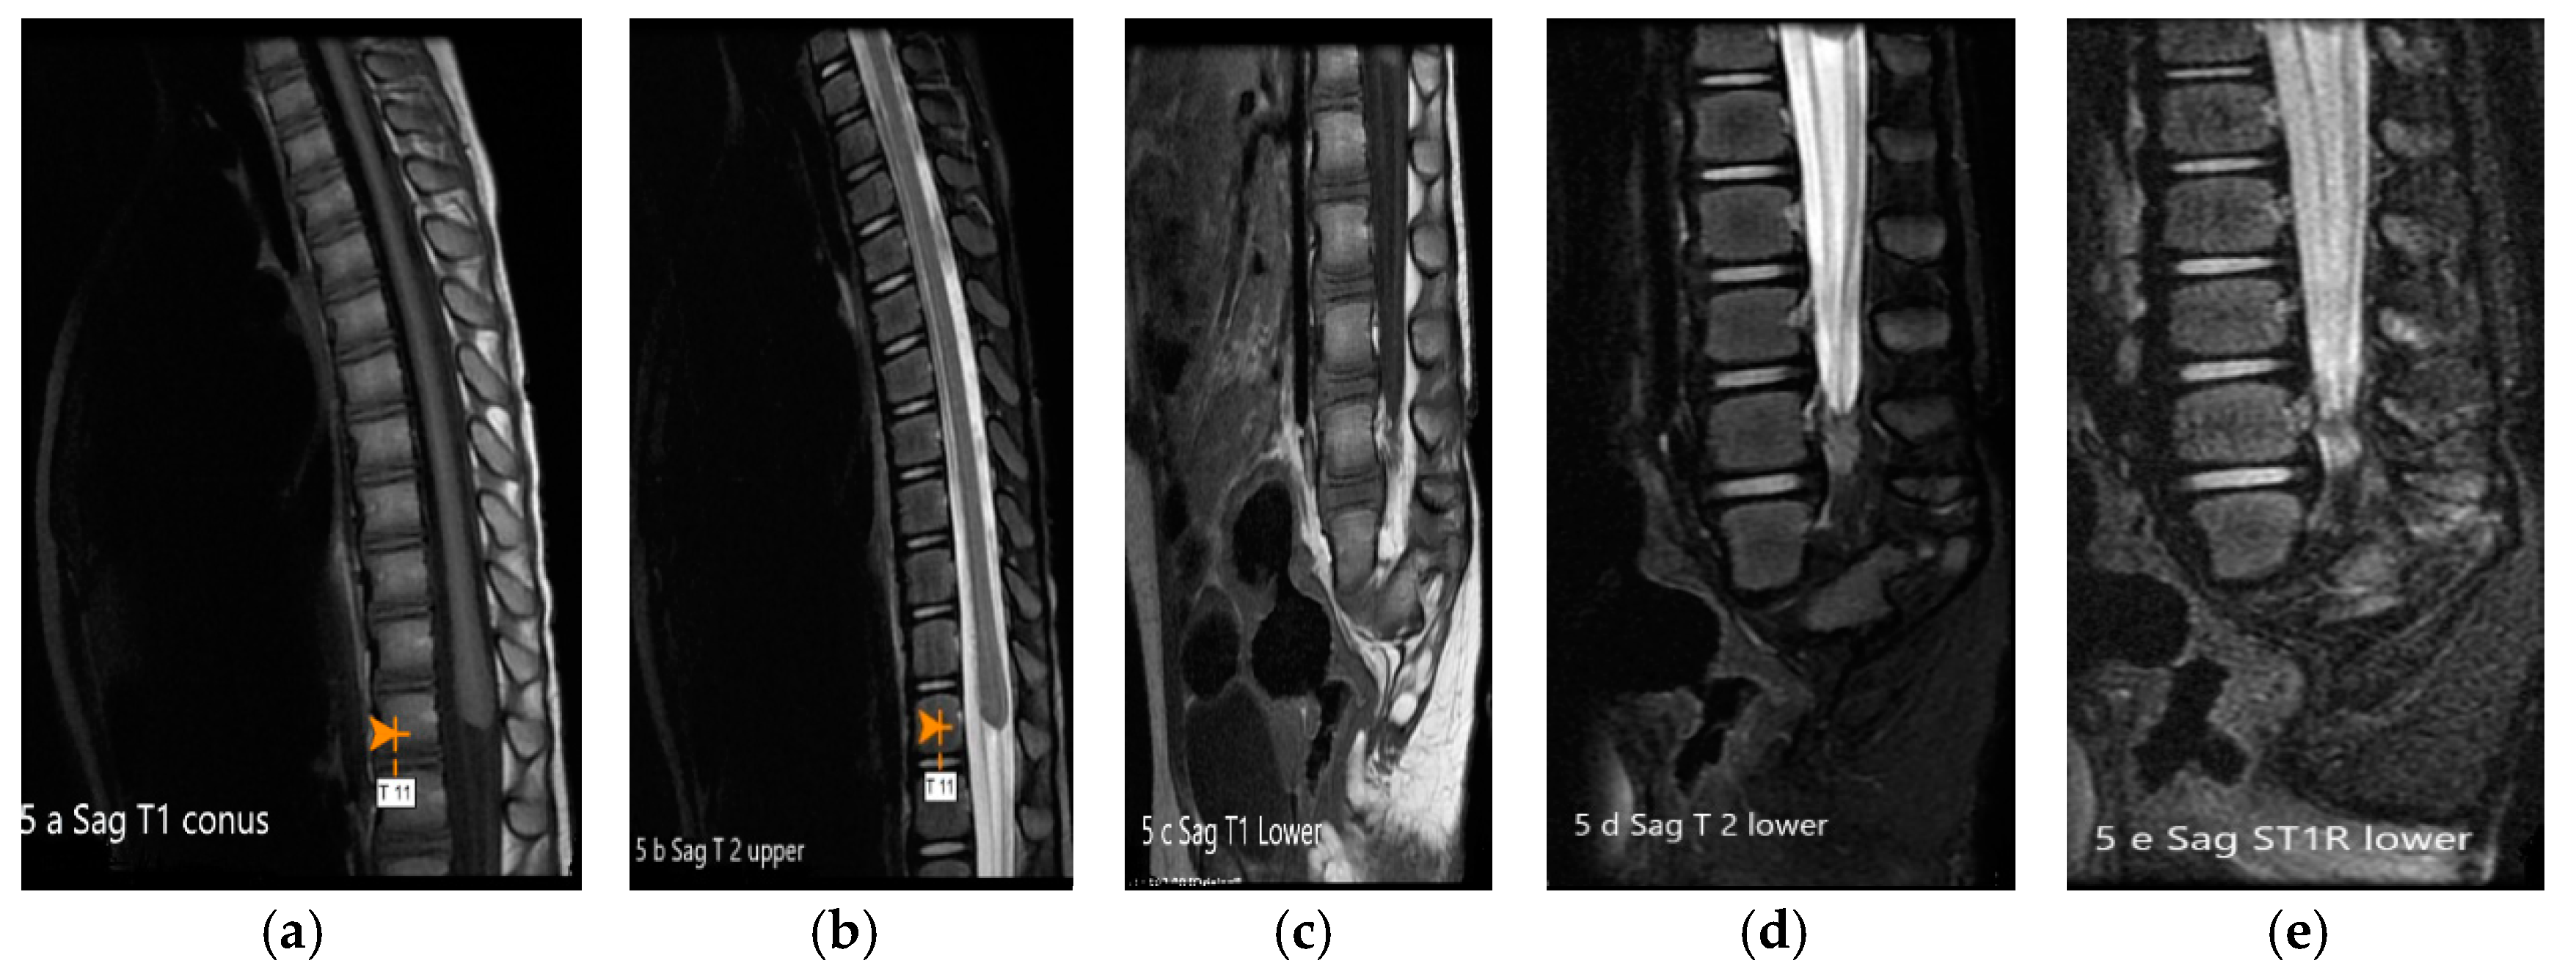

2. Case Presentation